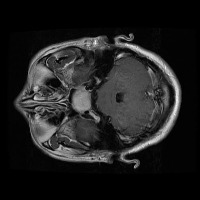

Early Detection of Brain Tumors: Use the "tesis" model to analyze MRI scans of patients proactively during routine check-ups, helping in the early identification of the presence of lesion selar or tumor hipofisario, leading to timely and potentially life-saving interventions.

Assisting in Treatment Planning: Oncologists and neurosurgeons can use the "tesis" model to study the location, size, and class of a patient's tumor. This helps in determining the best treatment options and surgical approaches, ultimately improving patient outcomes.

Medical Education and Training: Incorporate the "tesis" model in medical school curricula and professional trainings aimed at educating future doctors and radiologists about the identification and treatment of lesion selar and tumor hipofisario.

Research Tool for Cancer Studies: The "tesis" model can serve as a tool for researchers working on experimental treatments or clinical trials focused on lesion selar and tumor hipofisario. By identifying tumor classes efficiently and consistently, the model can help researchers compare treatment efficacy and study tumor progression over time.

Second Opinion Provider: Medical professionals can use the "tesis" model to double-check their own findings when analyzing brain MRI scans. This can reduce the likelihood of diagnostic errors and help confirm the presence of lesion selar or tumor hipofisario, resulting in more accurate decision-making.